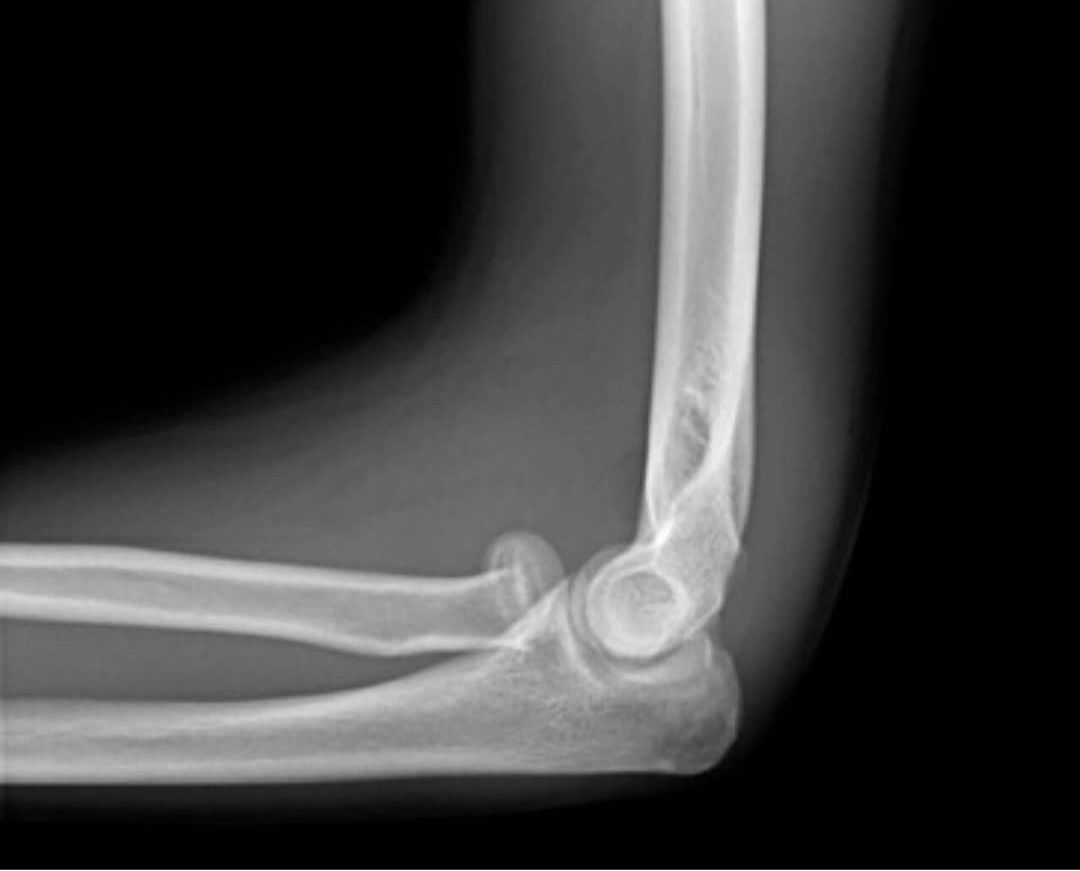

Fourteen years old boy with Salter harries type one fracture of the proximal radius and avulsion of the medical epicondyle.